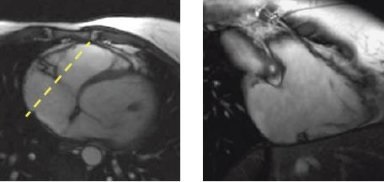

3. Prescribe an oblique coronal through the right ventricle.

1. Identify the atrio-ventricular groove of the RCA.

2. Prescribe a single oblique coronal slice through the right ventricle, perpendicular to the A-V groove using a gated 2D FIESTA or a 2D FastCine with FatSAT sequence.

Figure 2. Axial localizer with oblique prescription line (left), oblique coronal of right ventricle (right)